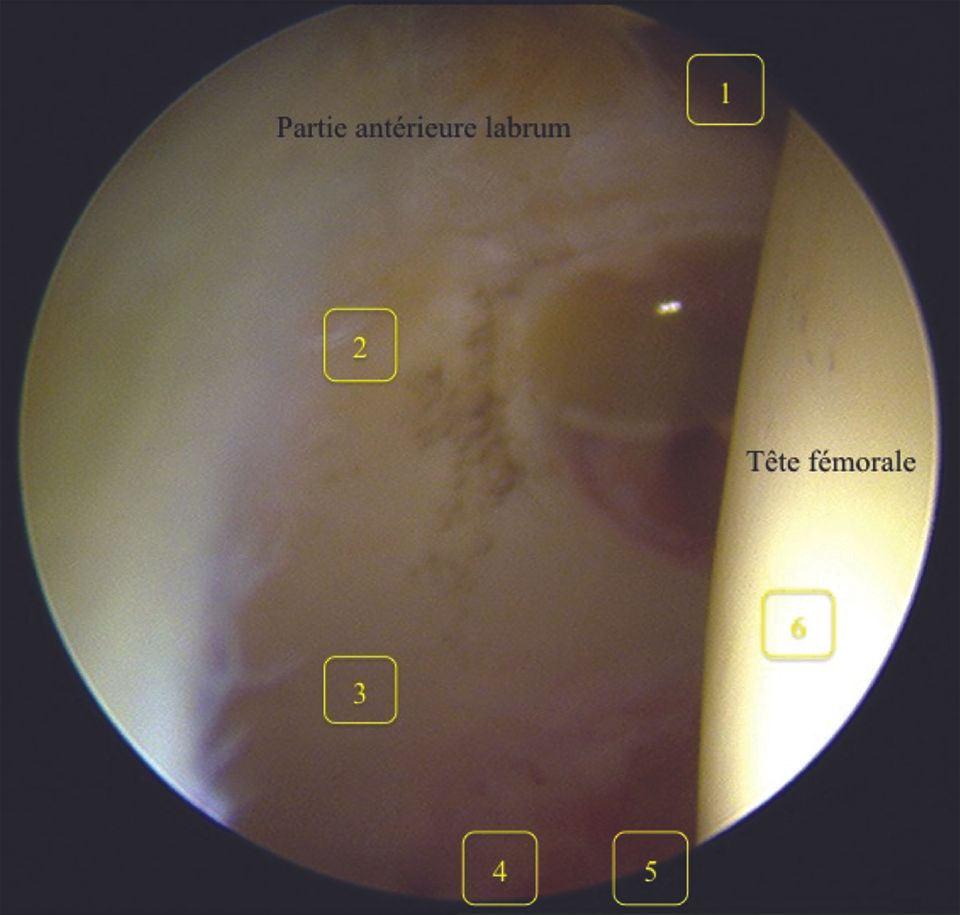

This technique, coupled with general anaesthesia and a neuromuscular blocker to aid the relaxation of the anterior iliofemoral ligament, allows a reduction in traction force (joint separation) from 500 N to 230–300 N (38,39), thus reducing the risks of potential complications (see “Complications”, above). Next, the nitinol guide is inserted into the spinal needle (Fig. 4). After withdrawing the spinal needle, the hollow trocar is introduced on the nitinol guide (Fig. 5) and the arthroscope is inserted. The arthroscopic view is shown in Figure 6.

What can be seen is the round femoral head, which faces the acetabulum (Fig. 6). Check that the camera is positioned perpendicular to the floor and that the scope is pointed upwards to show the triangular zone between the femoral head and the anterior part of the labrum (Fig. 7, right).